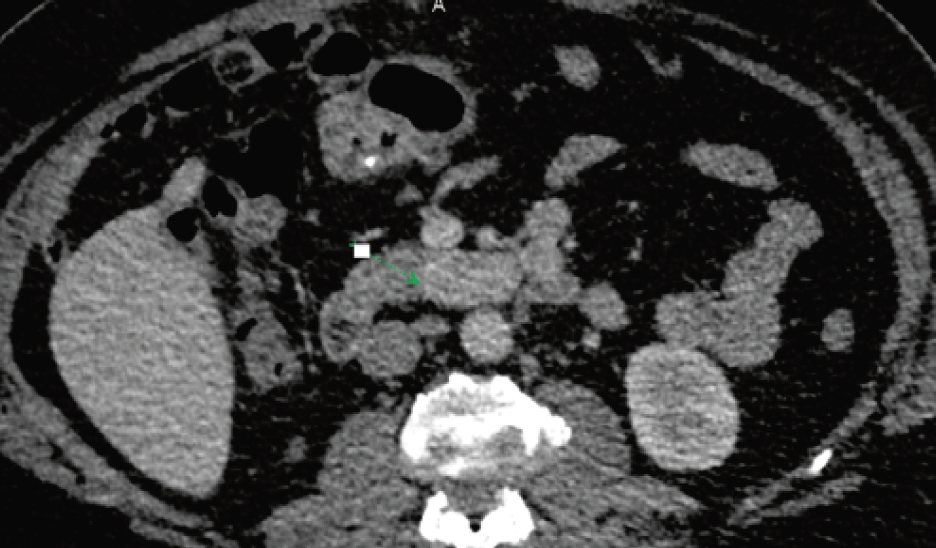

4. Fig. 1. MSCT of the abdominal cavity with CU. Izovascular formation in the hooked process of the pancreas, lymphadenopathy.

Subject

5. Fig. 2. MSCT frontal plane, tumor of the pancreatic head T2N1M0.

6. Fig. 3. MSCT frontal plane, pancreatic head tumor.